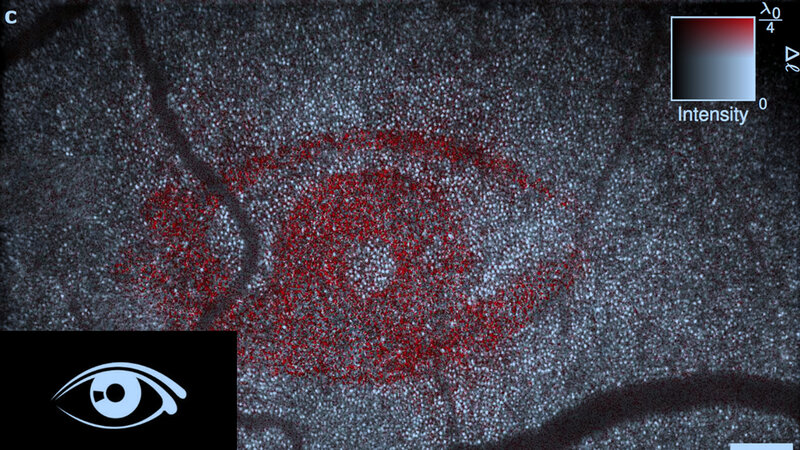

Der Arbeitsgruppe von Gereon Hüttmann, Institut für Biomedizinische Optik, und Dierck Hillmann, OCT-Forschung der Thorlabs GmbH, gelang es nur mit Hilfe numerischer Korrekturverfahren, unvermeidliche Bildfehler des Auges zu korrigieren und so einzelne Photorezeptoren sichtbar zu machen. Anschließend konnten sie auch deren Funktion detektieren: Sie beobachteten im Menschen, dass sich die Photorezeptoren bei Stimulation durch Licht um wenige Nanometer ausdehnten. Dies ist ein wichtiger Schritt auf dem Weg, die primären Sehvorgänge in den Photorezeptoren quantitativ zu vermessen.

Die Lübecker Forscher setzten ein neuartiges, selbst entwickeltes OCT-Verfahren ein. Statt die Netzhaut mit einem fokussierten Laserstrahl abzutasten, bildet dieses ein wenige Millimeter großes Feld auf einer Hochgeschwindigkeitskamera ab. Mit dem Gerät wird nicht nur die Stärke, sondern auch die Laufzeit des Lichtes mit bisher kaum möglicher Präzision bestimmt. So konnten die Forscher messen, wie sich die Zeit verändert, die das Licht braucht, um die Photorezeptoren zu passieren - und damit auf mögliche Änderungen in der Dicke der Photorezeptorzellen mit Nanometergenauigkeit zurückschließen. Das verwendete Verfahren basiert auf dem in Lübeck entwickelten Prinzip der Holoskopie, das bereits mit zwei Preisen ausgezeichnet wurde.